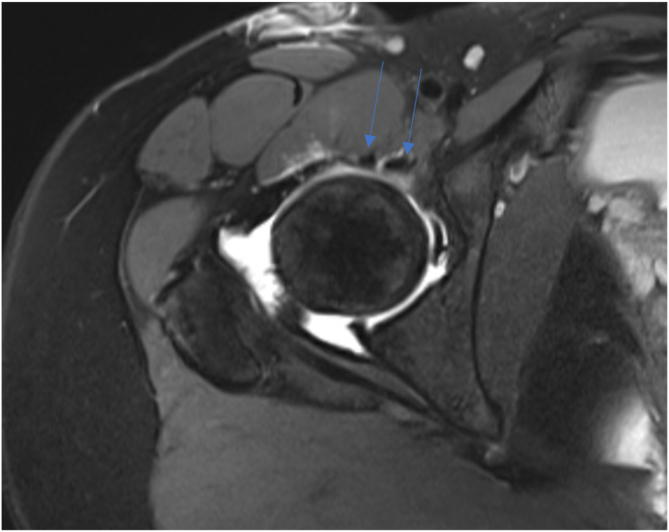

MRI scans of the operative hip as well as both control hips were evaluated by either an orthopaedic surgery fellow (M.M.) or resident (A.H.) to determine the number of iliopsoas tendons present at the level of the hip capsule (Figs 2 and 3). The number of tendons identified and released was recorded from the operative reports. All patients were treated with iliopsoas release between 2011 and 2020. Demographic data were gathered through retrospective chart review of enrolled subjects and included age at the time of surgery, sex, and subsequent hip operations.

Fig 2.

Magnetic resonance imaging slice (axial intermediate fat-suppressed sequence) showing bifid iliopsoas tendon (arrows) in right hip.